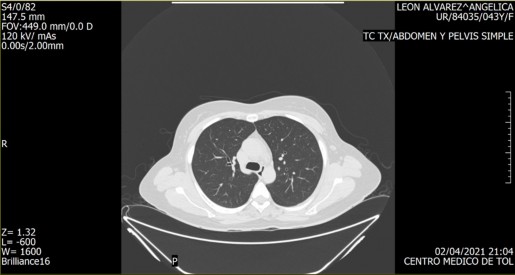

Imagen 1. TC TX. Abdomen y pelvis simple. Captura de video. (Autora, 2021).

Imagen 2. TC TX. Abdomen y pelvis simple. Captura de video. (Autora, 2021).

Imagen 3. TC TX. Abdomen y pelvis simple. Captura de video. (Autora, 2021)

Por supuesto, la producción artística no está exenta de un orden simbólico, mismo que determinará la relación de identificación imaginaria con la obra. Es a partir de esta lógica que se retomó una tomografía de tórax realizada ante un dolor inexplicable en el abdomen, inexplicable, porque le sucedieron diversos estudios que devolvían la interrogante sobre el origen del dolor en cuestión.

La tomografía señaló, entre otras cosas, la existencia de una “morfología ovoidea de bordes tenues y mal definidos, de densidad heterogénea, ya que presenta porciones sólidas y líquidas, mide en su conjunto 116x75mm en sus ejes mayores”. Cabe mencionar que, al revisar una y otra vez los videos que conforman el estudio, es imposible determinar dónde se encuentra la morfología ovoidea. Hay elementos que permiten una relación identificatoria, una pelvis, algún órgano, pero nada que pueda dar cuenta de la morfología en cuestión; fue necesario recurrir al orden simbólico de la medicina alópata para darle un nombre al elemento anómalo.

Adicionalmente, desde el ámbito imaginario se le nombró ‘Benedicto’, haciendo alusión a su carácter significante asociado a lo benigno, pero también al nombre del penúltimo papa, cuya imagen es asociada a un personaje nada benigno e incluso malvado. Bajo este nombre, fue posible establecer una identificación imaginaria con algo ominoso producido por el propio cuerpo y que, a partir de la tomografía, tenía una ambivalencia propia de Schrödinger: era al mismo tiempo benigno y maligno, y solo una intervención quirúrgica podría determinar su estado final.